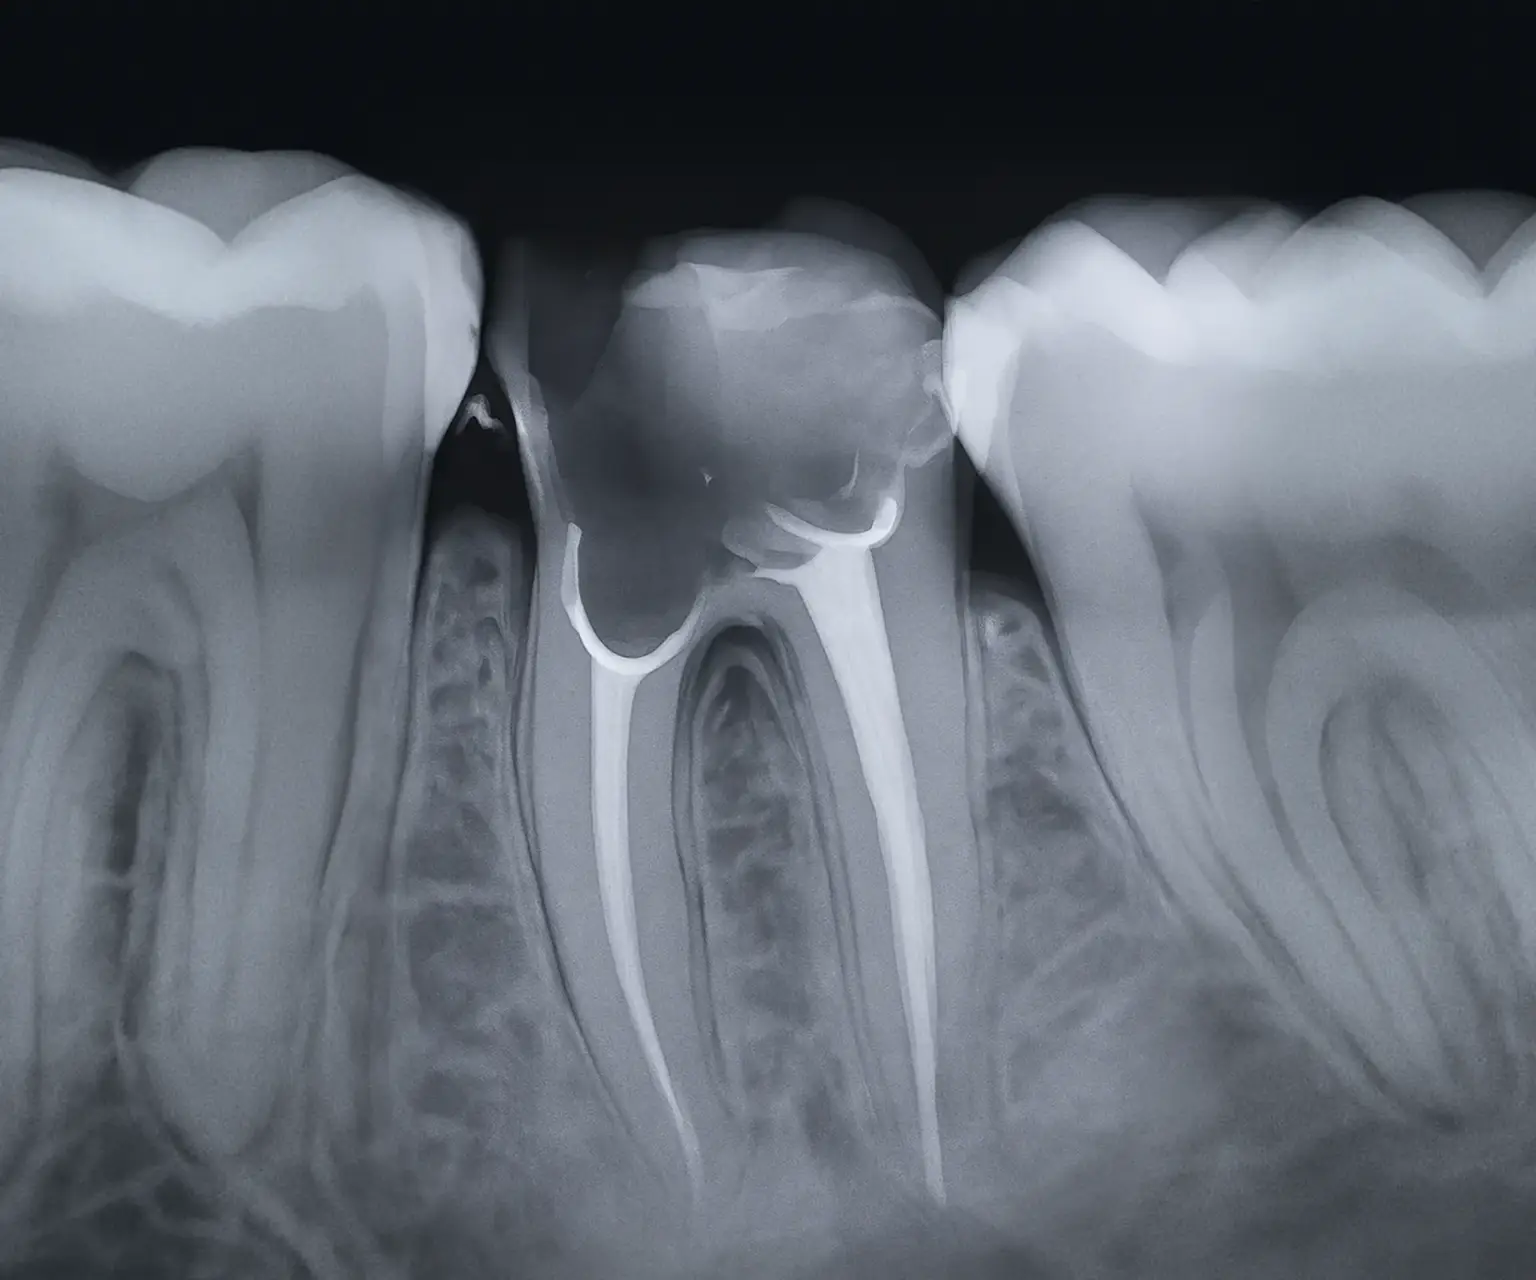

Intraoralna snimka zubi – preciznost u fokusu

Intraoralna rendgenska snimka omogućuje izuzetno detaljan prikaz pojedinačnih zuba ili manjih regija usne šupljine. Idealna je za otkrivanje karijesa, problema s korijenom zuba, provjeru ispuna i statusa oko zubnog živca. Zahvaljujući digitalnoj tehnologiji, rezultati su trenutno dostupni i spremni za analizu.